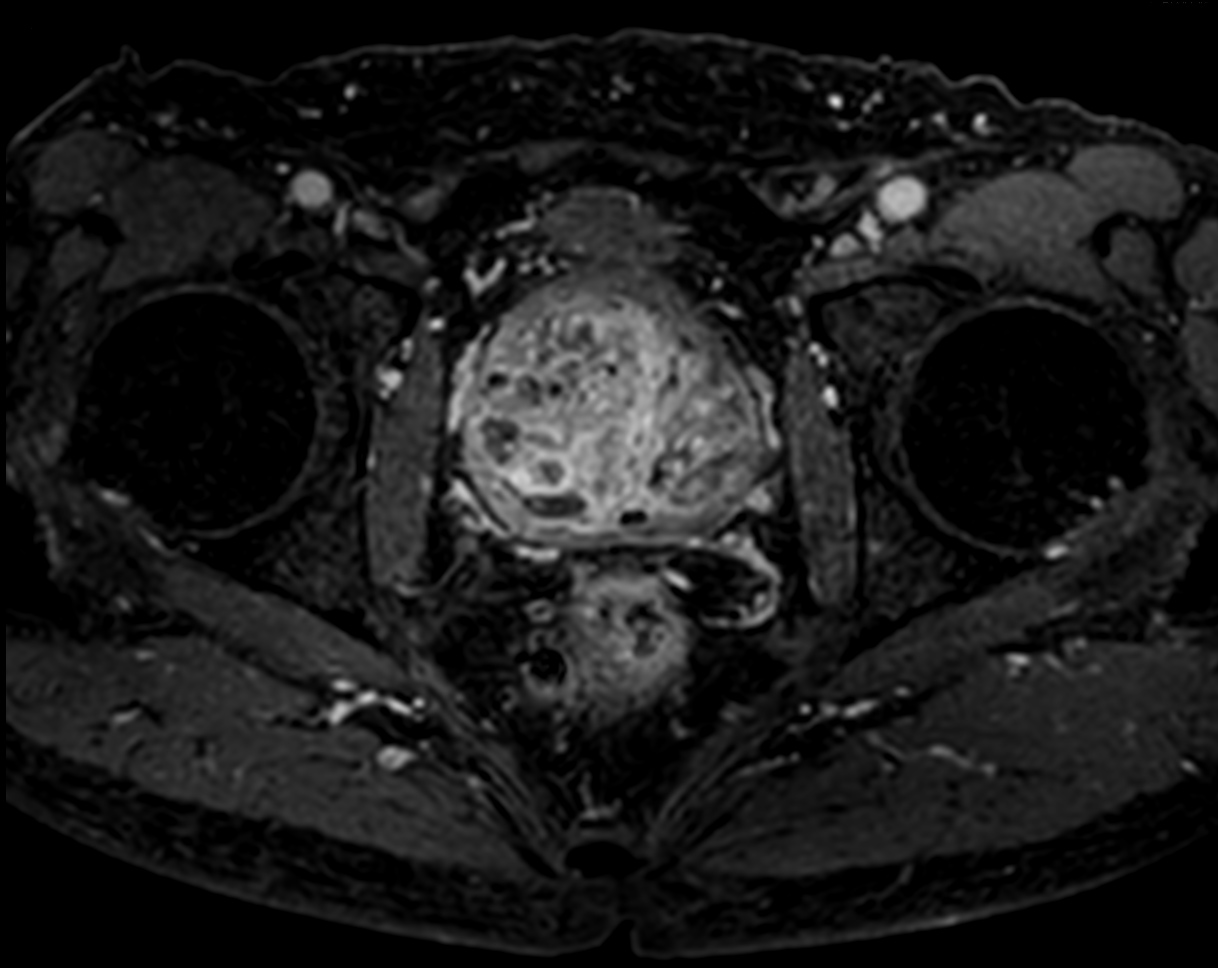

Multi-phase, contrast-enhanced prostate imaging

Patient with a prostate lesion. The ExamCard includes techniques for 3D imaging (PelvisVIEW, eTHRIVE) allowing for multiple image directions in one single scan, efficient fat-free imaging over large field-of-views (mDIXON XD), a multi-phase contrast-enhanced sequence (4D FreeBreathing) to improve imaging confidence and Compressed SENSE to accelerate the entire exam.

T1w mDIXON XD FFE Compressed SENSE